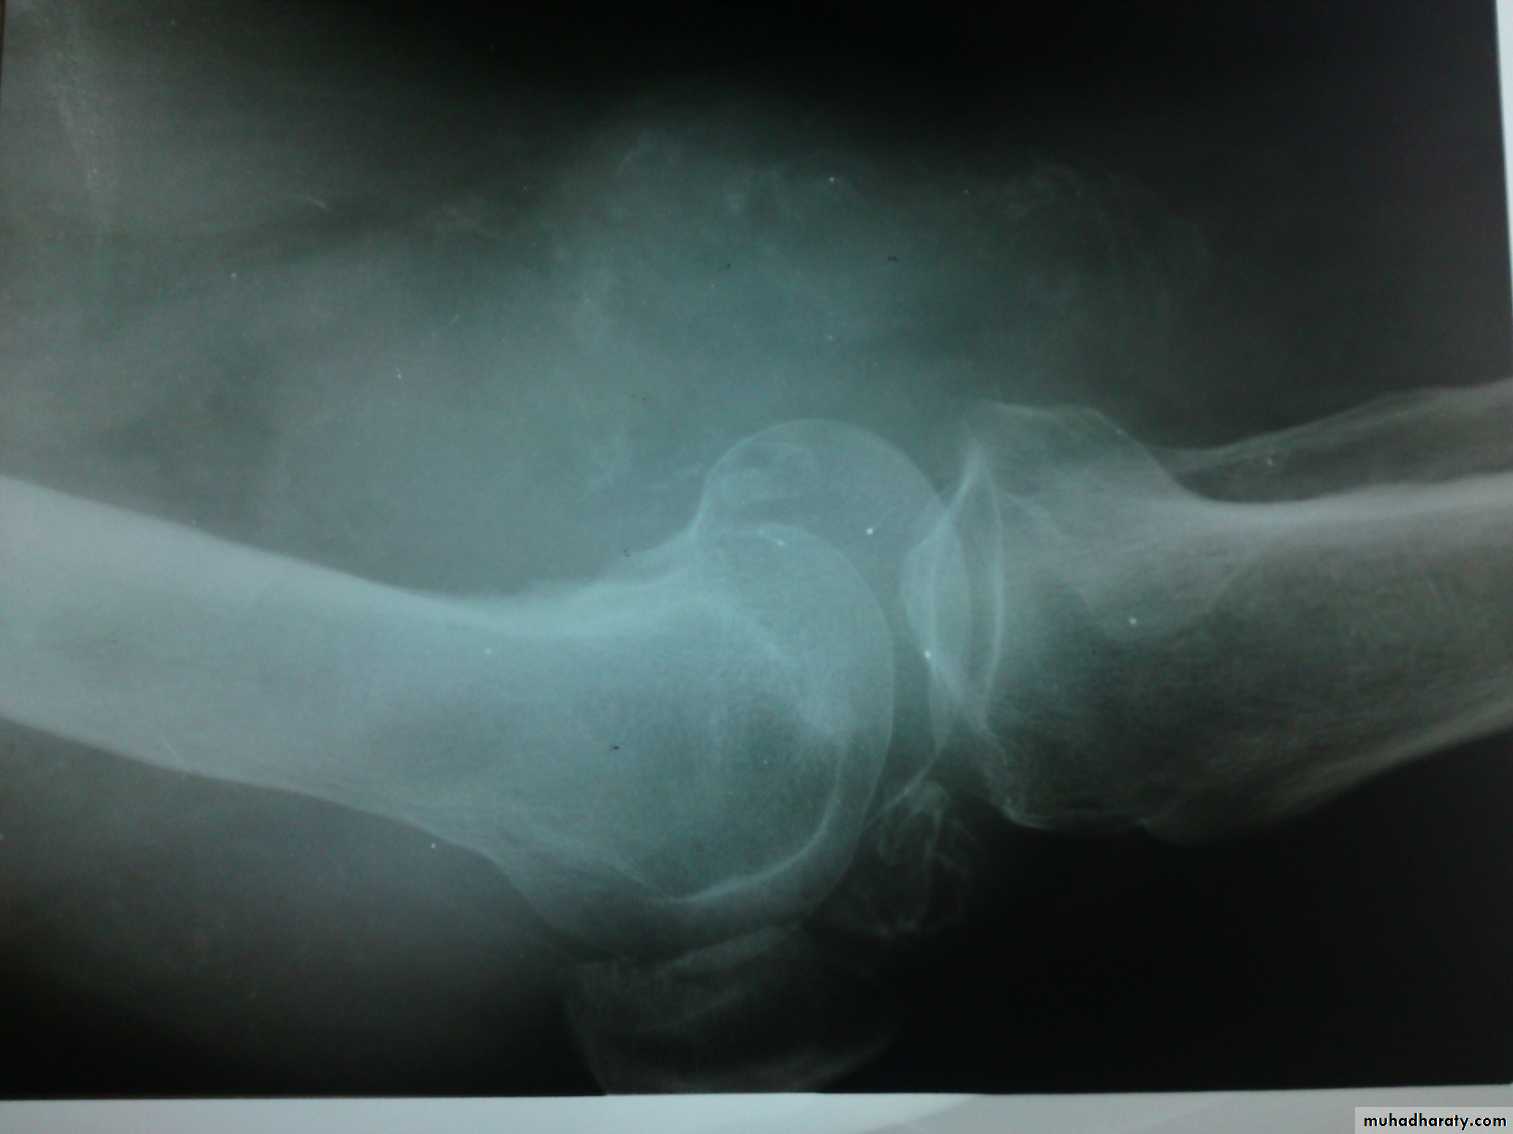

Shape:Decreased joint space and oseophytes in osteoarthritis.

Dislocation or subluxation.

Density: increased in chondrocalcinosis, loose bodies…

Calcification in knee jointsynovial carcinoma